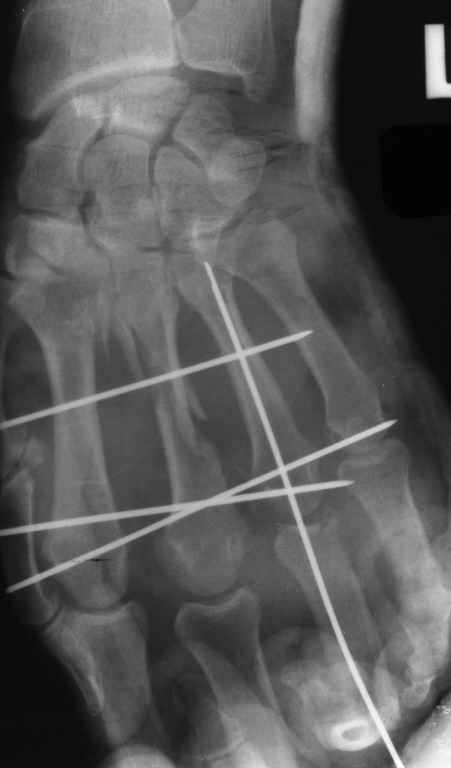

Диагноз: Стойкая Смешанная дермотеногенная контрактура 3,4 пальца правой кисти.